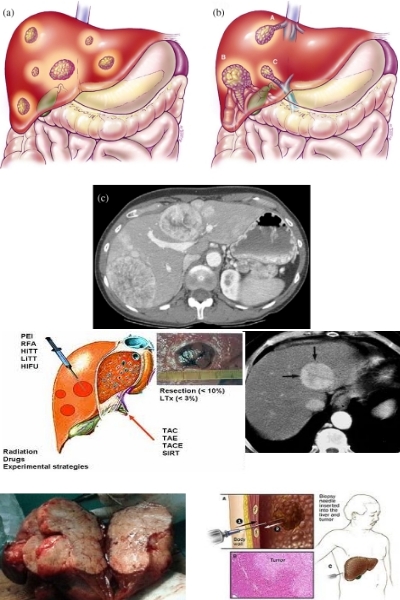

Tumore Del Fegato E Cirrosi Il Carcinoma Epatocellulare

Tumore Del Fegato Fondazione Umberto Veronesi

Tumore Del Fegato E Delle Vie Biliari Istituto Nazionale

Malattie Del Fegato Roma Dott Prof Iannetti Cancro